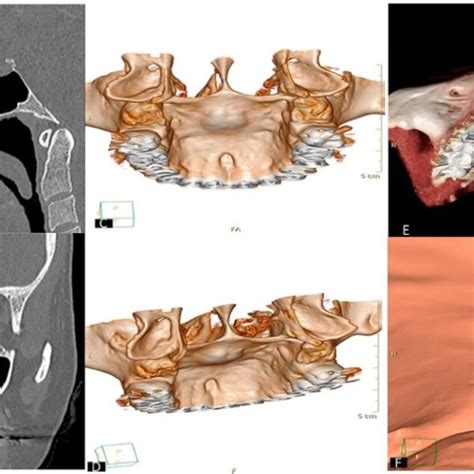

- Quiste nasopalatino: Es un quiste que se forma en el conducto nasopalatino (cerca de los incisivos centrales superiores). Cuando crece, puede abultar el paladar anterior con una hinchazón lisa.

- Pruebas complementarias: Dependiendo de lo que sospeche, puedo solicitar una radiografía (por ejemplo, una radiografía periapical o panorámica si sospecho de un origen dental o un diente extra), o incluso una biopsia.